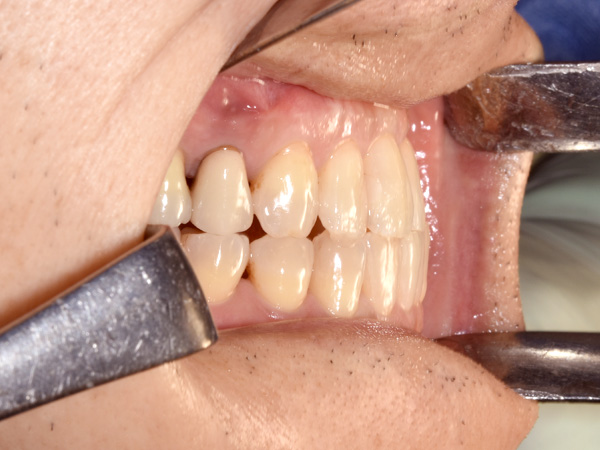

右側のかみ合わせを確認しています。

頬っぺた側、舌側の粘膜を伸展させます。